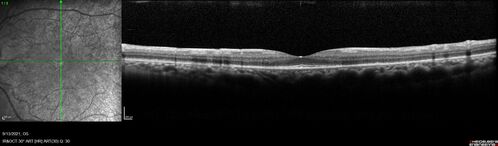

Ocular Lymphoma - Initially presented like auto-immune retinopathy

43 year old man: initial presentation - The vision in the left eye is blurry and opaque for about 2 weeks.  In the central of the vision, when he covers the right eye, in the center of the left eye there is a film with a light in the middle.  This has never happened before.  He has not been sick for the last few months.  A few weeks ago he saw waves on the floor when looking down but that has gone away.  Since the vision loss started the vision has not changed much.  The central vision is not getting better.

VA improved over 2 months to normal.  Then the patient had 2 more episodes of self-limited vision loss (no treatment).  Then 2 years later he presented with a diagnosis of CNS lymphoma and later developed subretinal deposits (last images)